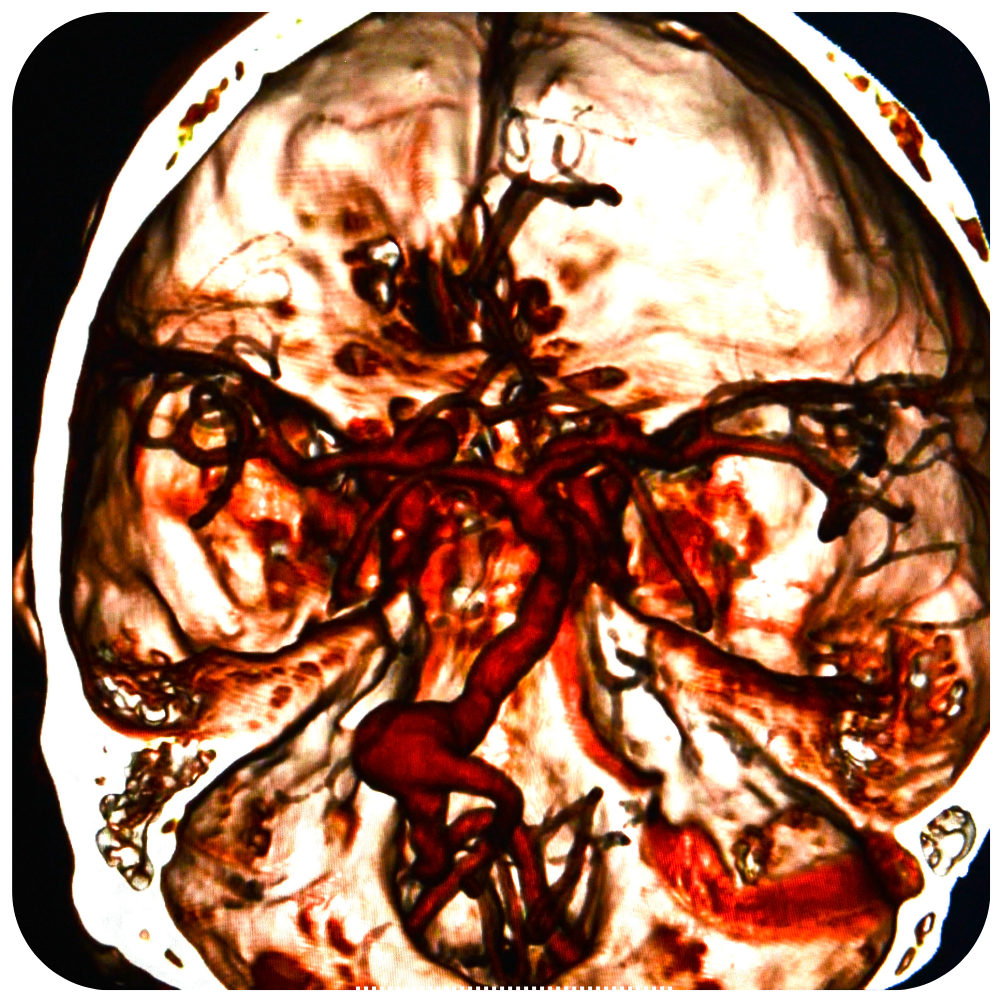

Craneotomía Operación en la que se extrae un pedazo del cráneo. Una craneotomía se realiza para que los médicos puedan extraer un tumor o tejido anormal del cerebro. También se puede realizar para extraer sangre o coágulos del cerebro, aliviar la presión en el cerebro después de una lesión o…